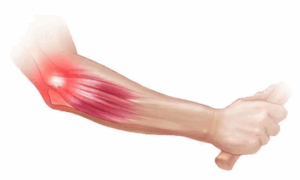

Tendinitis (all)

Tendinitis is inflammation of the thick fibrous cords that attach muscle to bone. These cords are called tendons. The condition causes pain and tenderness just outside a joint.

Tendinopathy

Tendinopathy is a term for any condition that affects a tendon. Tendons are cords that attach muscle to bone. Tendinopathy, which can cause pain and tenderness, is common. It is often caused by overuse or repeated movement and tends to affect certain tendons in the arm or leg.